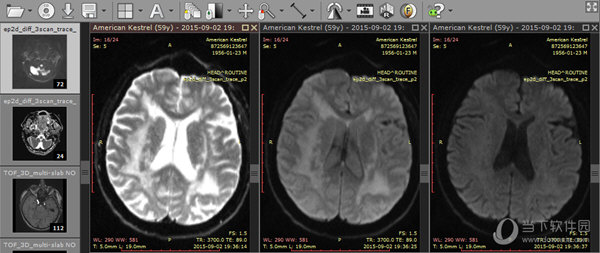

6、多系列观赏:可以在多个面板中同时打开多个系列的一个或多个研究用于比较。